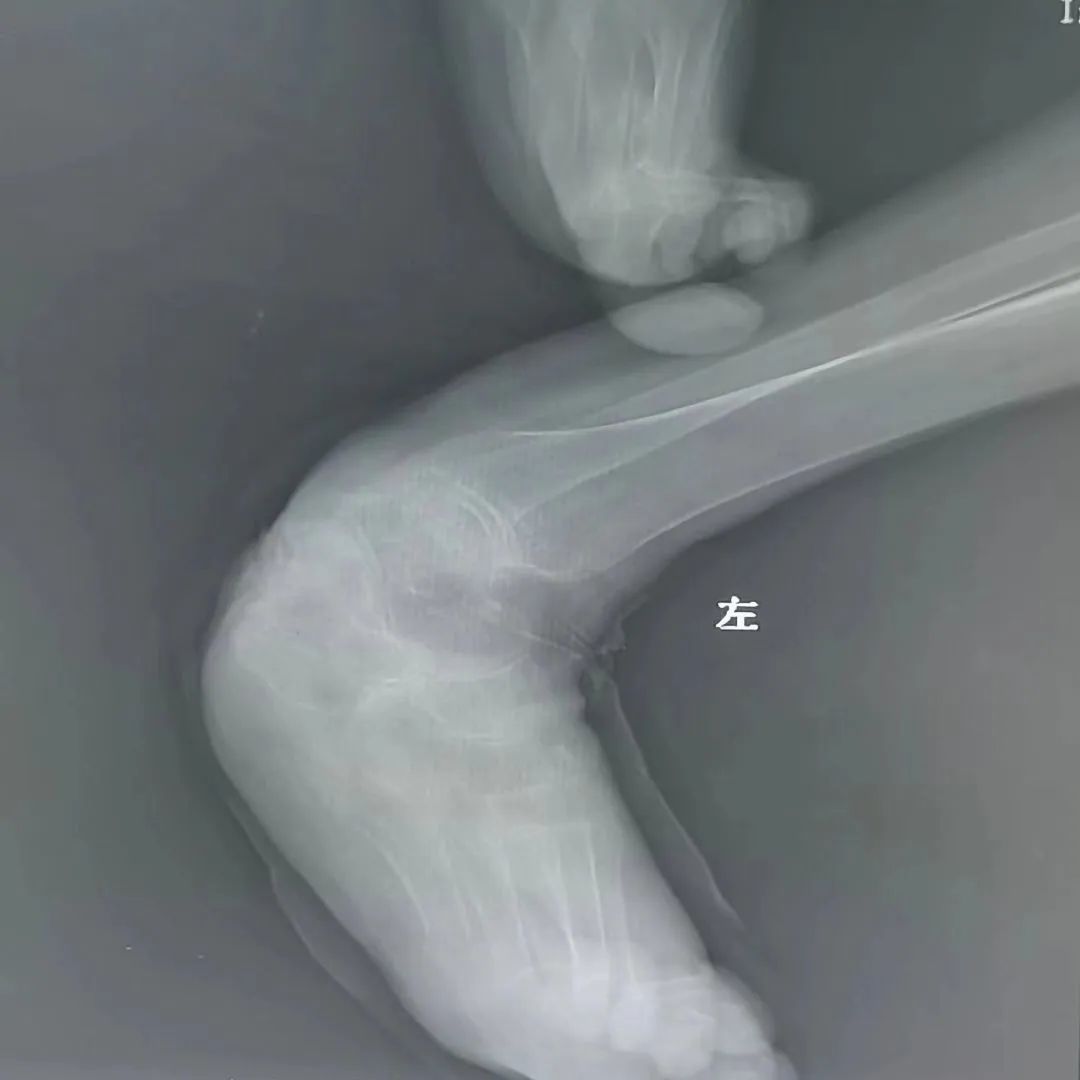

该患者伴有严重的类风湿性关节炎并肢体畸形

经过细致的检查评估,曹玮主任决定采用目前国际上较为成熟的“脊髓电刺激”疗法来为张阿姨治疗糖尿病足性疼痛,并避免截肢。脊髓电刺激治疗是一种微创疼痛治疗技术,它是在脊髓的硬膜外后间隙插入一根电极,通过电刺激阻断疼痛信号的传导,同时可调控交感神经以改善糖尿病足的末梢血运循环。但是由于张阿姨长期患有类风湿性关节炎,脊柱及四肢严重畸形,无法俯卧位,且椎管多节段狭窄,常规操作无法将电极植入脊椎预定位置,为治疗带来了很大难度。为此,曹玮主任及其团队决定创新采用血管鞘介入技术辅助电极植入,用穿刺针成功引入导丝、导管及血管鞘,通过血管鞘成功建立电极植入通道,之后成功将电极植入至硬膜外脊髓背侧预定的相应刺激区域。在术中测试及术后随访中,张阿姨表示下肢疼痛明显减轻。